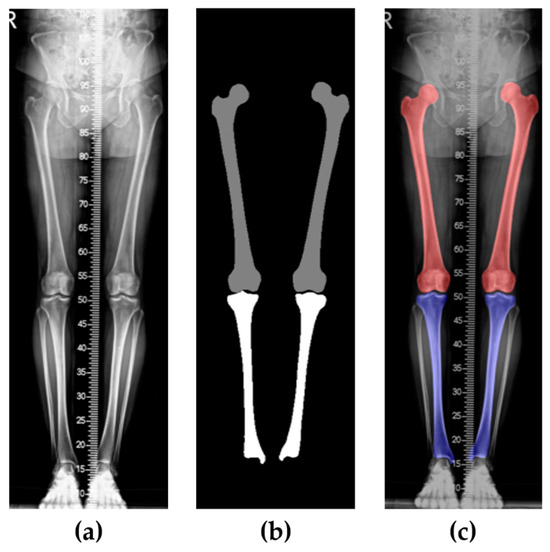

- Semantic segmentation (for detail, see Section 2.3.1): first, the preprocessed lower-limb X-ray images are semantically segmented into two classes, the femur and tibia.

2.3.1. Femur and Tibia Segmentation

- i.

- Select the two largest femur and tibia regions:Let be the segmented image, where for femur and for tibia.

- ii.

- Identify connected regions:where represents connected components of femur and represents connected components of tibia with denoting the index of each connected component and j = 1, 2 specifying femur(j = 1) or tibia (j = 2)

- iii.

- Select the two largest regions:where and are the selected femur regions and and are the selected tibia regions.

- iv.

- Calculate the centroids of each femur and tibia regions:where the selected regions .

- v.

- Classify, based on centroid coordinates: